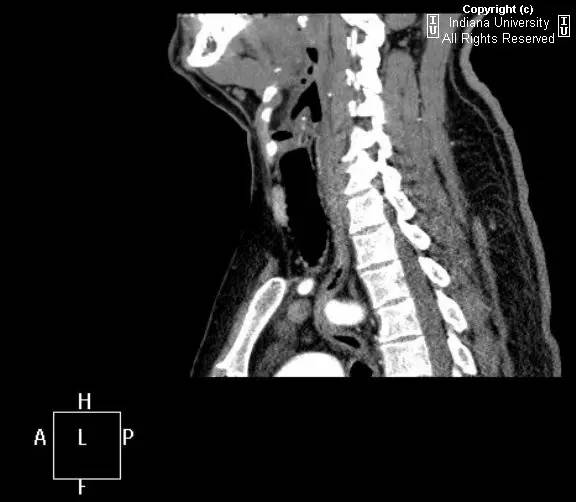

【影像学表现】胸部平片示右位主动脉弓,肺动脉突出,双肺清晰。CT示右位主动脉弓,并右位降主动脉,迷走左锁骨下动脉起自后方,从食管后走形形成血管环。迷走左锁骨下动脉与憩室相关(Kommerell)。食管因左锁骨下动脉及憩室而向前移位。

【诊断】右位主动脉弓并血管环形成、迷走左锁骨下动脉并Kommerell憩室

Right-sided aorticarch, with vascular ring and aberrant left subclavian with Kommerell\’sdiverticulum